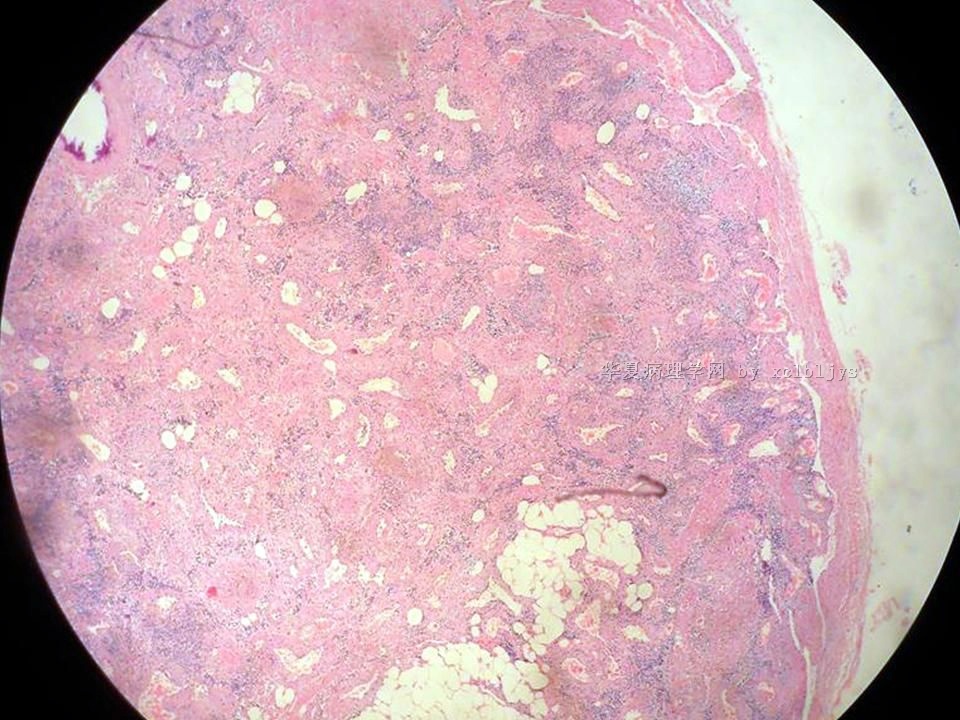

| 以下是引用xclbljys在2010-12-22 17:20:00的发言: 本例我们科室医生有两种意见:一种是炎性假瘤;第二种意见是炎性假瘤伴局限性Wegener肉芽肿。 依据是眼眶内肿块含有大量的动脉内膜炎改变,浸润的炎细胞有淋巴细胞、浆细胞、嗜中性粒细胞和嗜酸细胞等,如图16所示,炎细胞已经浸润动脉壁全层,应符合坏死性小动脉炎,但尚不能确定动脉壁弹力纤维层的破坏。 请各位老师点评! Wegener肉芽肿多发生在上呼吸道、肺、肾脏和皮肤等器官与组织。坏死性血管炎需证实有纤维素样坏死。小动脉炎多在皮肤病变比较明显。本例的小动脉炎或许是炎症引起的继发性改变。需要完善病史,查血免疫指标,看有没有系统性疾病。如果没有系统性疾病,还是考虑慢性炎症继发小血管炎。

血管炎是正常营养/供给血管的炎症性病变,而不是增生血管的炎症。血管炎往往有明显的临床相应症状,如皮疹。典型的Wegerner肉芽肿病有三联症(上呼吸道、肺、肾脏病变)。血管炎不仅是有炎症细胞,同时有血管壁的变性、坏死(纤维素样), 内皮细胞的变质和增生,炎症细胞浸润(包括中性粒细胞、淋巴细胞、组织细胞、嗜酸性细胞、巨细胞等)。不同类型的血管炎累及的血管大小、炎症细胞的类型、有无肉芽肿改变都不相同。血管炎的病因可以是过敏、自身免疫、胶原性疾病、感染等多种因素。